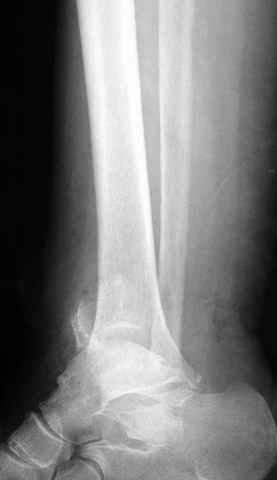

Pilon fracture:

Из работ Ramsey and Hamilton, Yablon et., укорочения на 1мм

малоберцовой кости, уменьшает на 42% контактную поверхность между

малоберцевой и таранной кости, которое в свою очередь приводит к

увеличению давления на остальные части суставной поверхности, что

является предпосылкой раннего артроза.

The unsatisfactory clinical results sometimes associated with slight widening of the ankle mortise and 42% reduction in the area of contact

between the tibia and talus with one millimeter of lateral displacemet emphasize the importance of restoring the normal roentgenographic relationship of the talus to medial malleolus after ankle

injures. Since the stress per unit area increases as the total area decreases, a decrease in contact area may be a factor contributing to a poor result after ankle or dislocation when talar displacement is one millimeter or more.